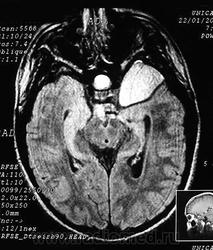

Полимикрогирия.

Приложения:

11.open-uri20120221-1537-7q7aumpolimikrogiriya_mikrogiriya_poligiriya.jpeg